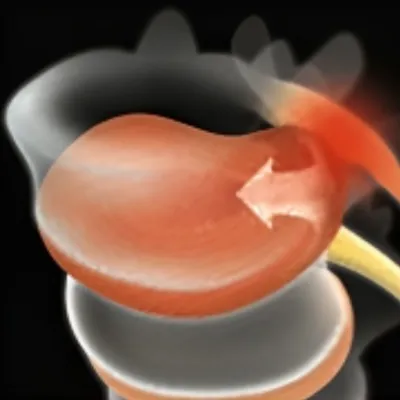

Our Advanced Laser-Enhanced Spinal Decompression™ Therapy is designed to gently stretch the spine, creating negative pressure within the discs. This process encourages the retraction of bulging or herniated discs and promotes the influx of healing nutrients, reducing inflammation and pain. Our unique methods relieve tension and pressure on the spinal discs, moving the affected parts of the spine back to their natural position. Additionally, the increased blood flow introduces more nutrients to the discs, promoting healing from within and significantly improving patient outcomes.

3) Allows disc absorption of gelatinous core

4) Reduces pressure on nerves

Our treatment technique targets your spinal nerves at the source to generate new cartilage and reduce inflammation and swelling around affected discs and joints, enabling damaged tissue to repair itself faster than usual. This is such a relaxing & painless process, that most of our patients fall asleep during their session!